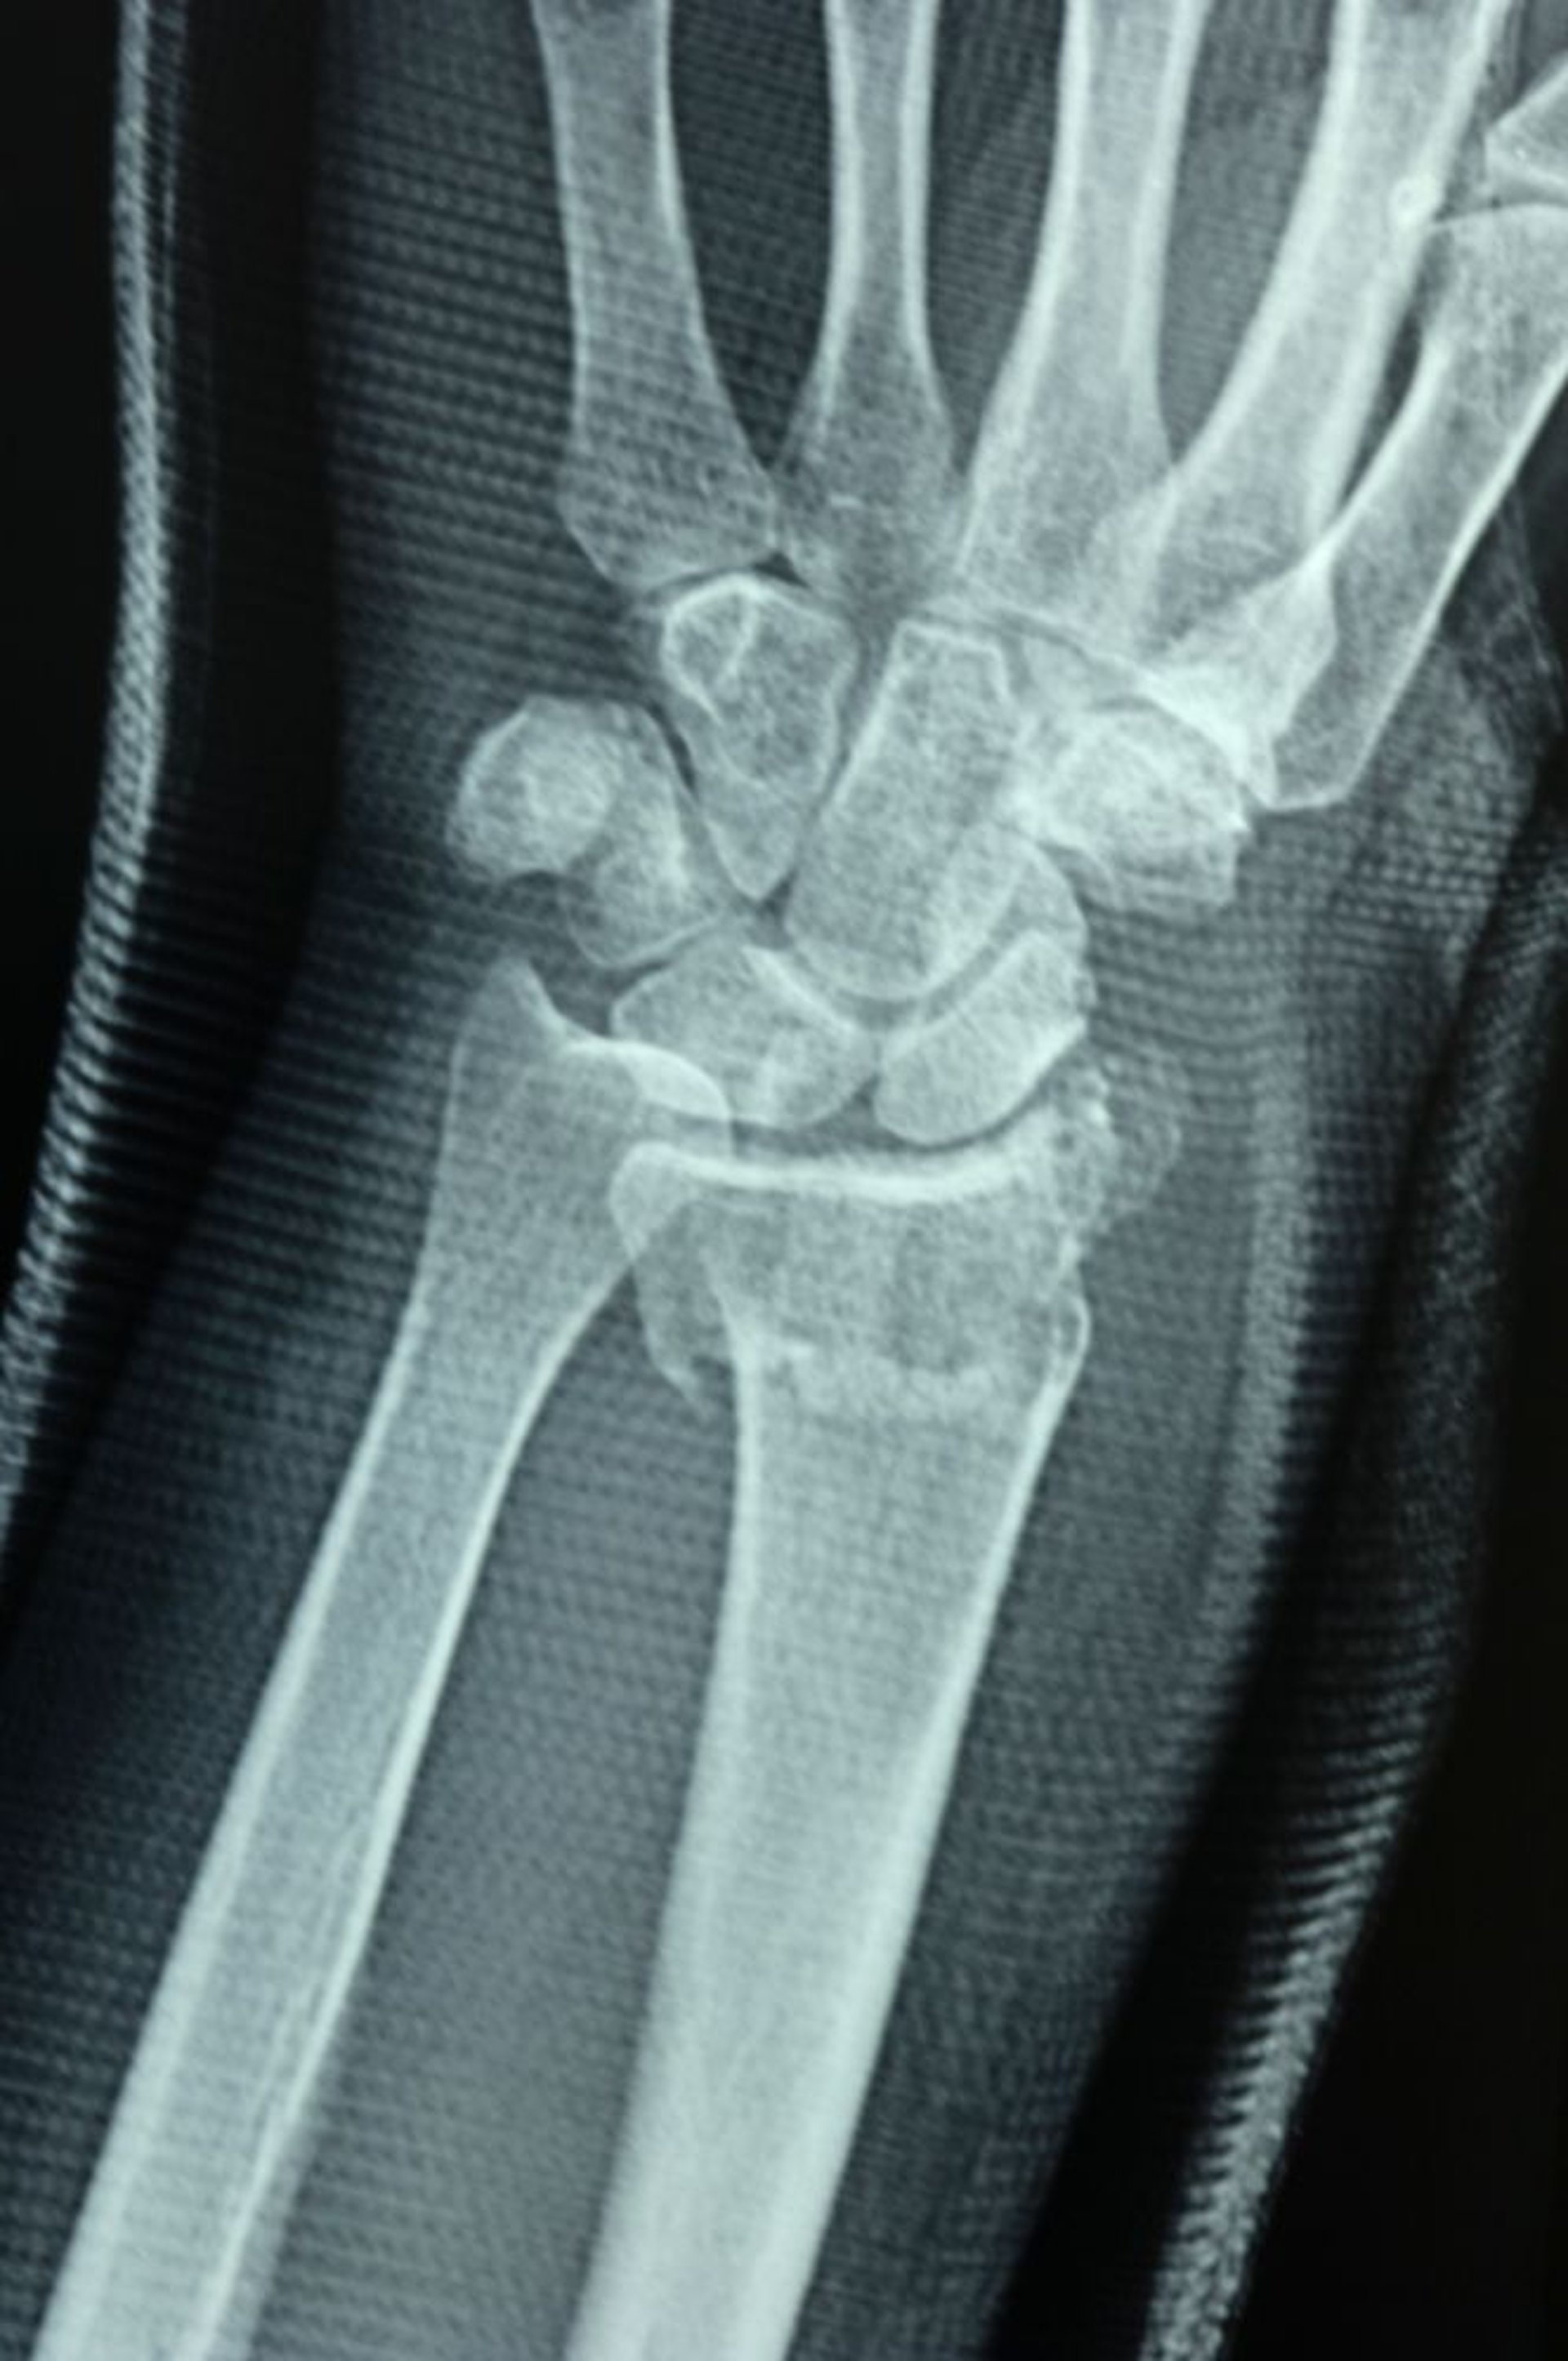

Fratura distal do rádio

A articulação radioulnar foi rompida, como mostra a falha do alinhamento das superfícies articulares da parte distal do rádio e da ulna, causando uma deformidade em degrau.